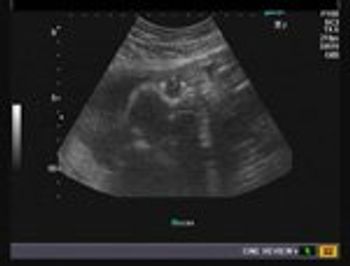

These are ultrasound images from a normal 3rd trimester fetus. What fetal anatomy do you see?